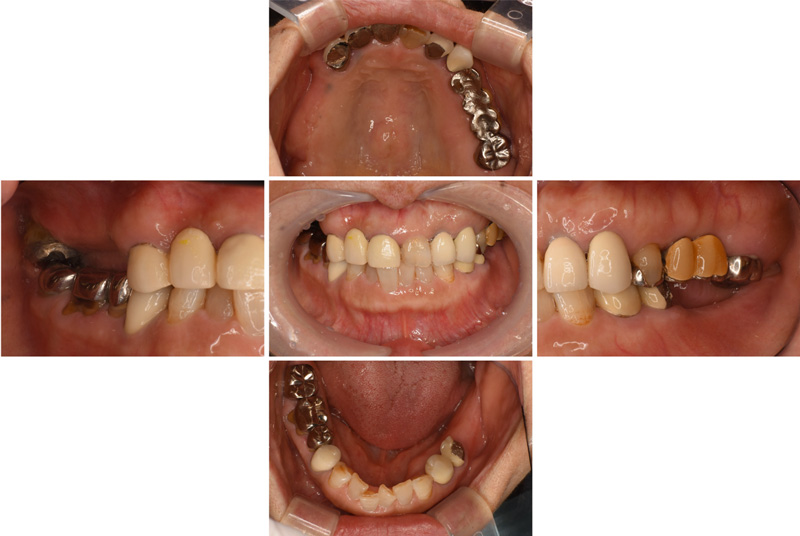

46歳女性

治療後